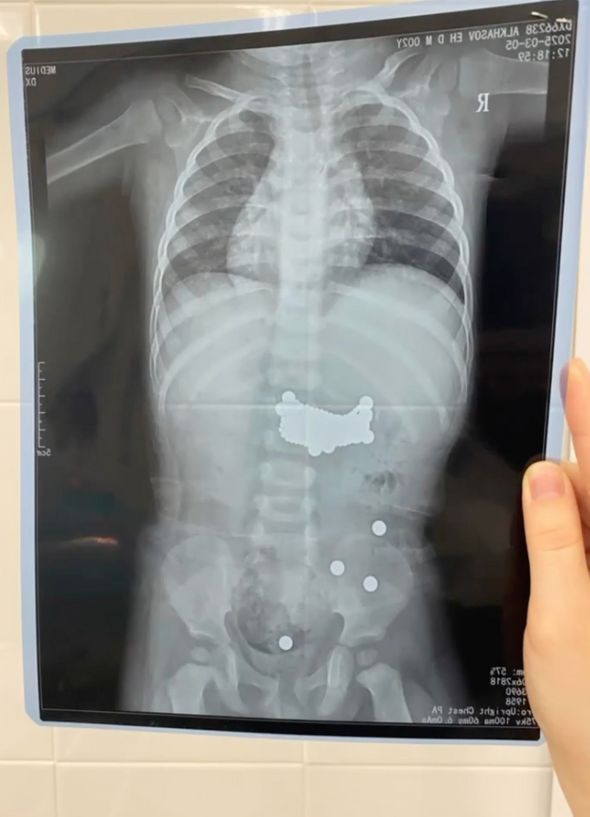

Дагестанские врачи спасли годовалого ребенка, проглотившего около 400 магнитных шариков, но он остается в реанимации

В Дагестане врачи прооперировали годовалого ребенка, проглотившего более 390 магнитных шариков от конструктора «Неокуба». Как сообщает тг-канал Детской республиканской клинической больницы имени Кураева, пациент в тяжелом состоянии остается в реанимации.

«В нашу клинику поступил ребенок проглотивший более 390 магнитных деталей конструктора. Дежурная бригада хирургов экстренно прооперировала пациента. На данный момент ребенок находится в отделении реанимации и общей терапии без дополнительных ухудшений, гемодинамика стабильная, не ест самостоятельно, получает парентеральное питание, проводится интенсивная терапия, коррекция всех жизненных функций, мальчик на ИВЛ, состояние тяжелое, стабильное», — рассказала завотделением клиники Марият Ахмедханова.